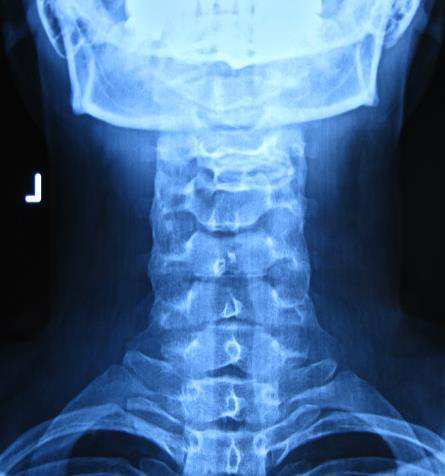

일자목과 디스크를 진단 받은 환자를 추나요법으로 치료한 사례

20대 여성이 목디스크로 인해 만성적인 목의 통증과 어깨 통증으로 내원하였으며 추나요법으로 호전된 치료사례